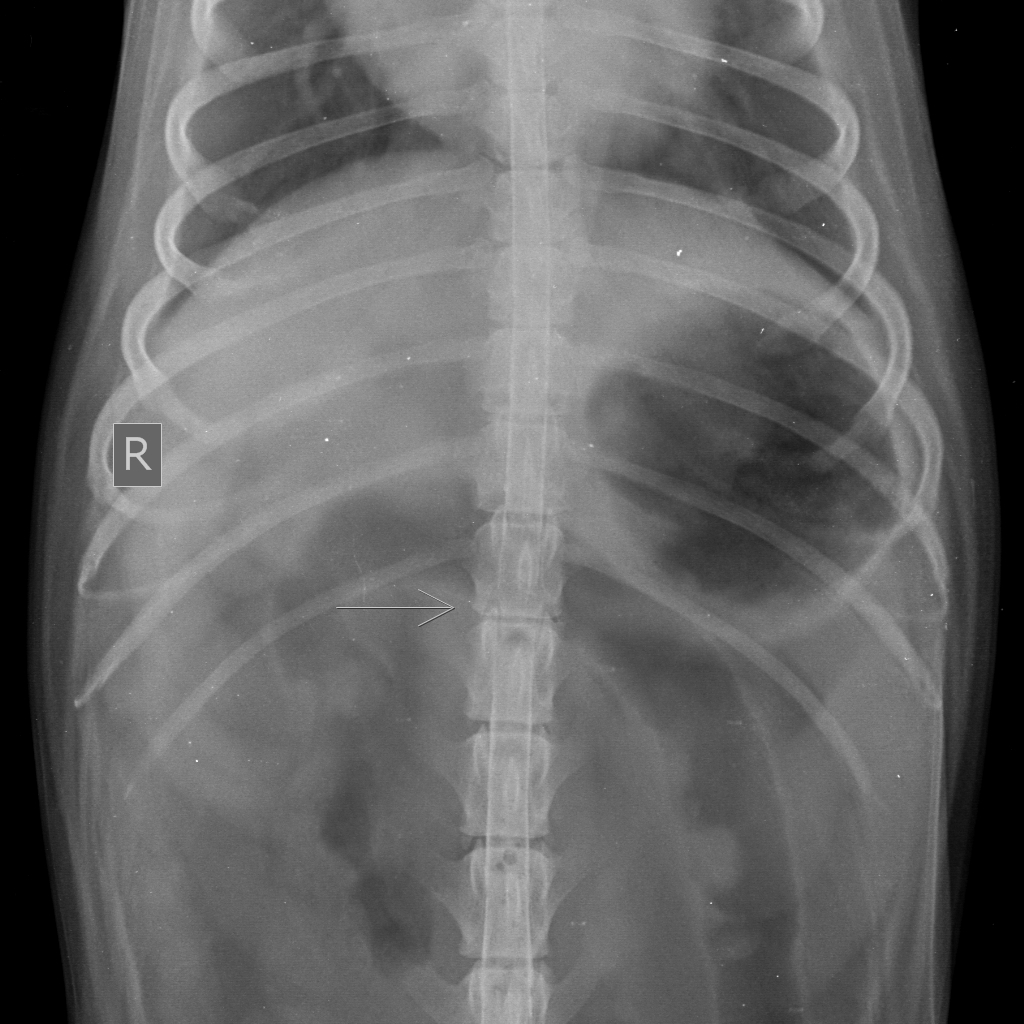

Рентген для животных. Вредно и Опасно?

Рентгенодиагностика (рентгенологическая диагностика) — распознавание заболеваний различных органов и систем на основе данных рентгенологического исследования. Рентгенодиагностика позволяет выявлять патологию, что очень важно для постановки точного диагноза и выбора последующей тактики лечения, определять локализацию и распространенность патологического процесса, взаимоотношение с соседними органами и влияние на их функции, устанавливать фазу развития заболевания, наличие или отсутствие осложнений, выявлять сопутствующие заболевания и др. Для рентгенодиагностики некоторых органов и систем (костей, сердца, легких) имеются естественные условия контрастности, другие же системы и органы могут стать объектом рентгенодиагностики лишь при условии создания искусственных контрастов, путем введения в эти органы специальных контрастных сред или веществ. Рентгеноконтрастные средства – различные химические вещества, которые при введении в организм улучшают изображение исследуемого объекта, увеличи

Рентгенодиагностика (рентгенологическая диагностика) — распознавание заболеваний различных органов и систем на основе данных рентгенологического исследования. Рентгенодиагностика позволяет выявлять патологию, что очень важно для постановки точного диагноза и выбора последующей тактики лечения, определять локализацию и распространенность патологического процесса, взаимоотношение с соседними органами и влияние на их функции, устанавливать фазу развития заболевания, наличие или отсутствие осложнений, выявлять сопутствующие заболевания и др.

Для рентгенодиагностики некоторых органов и систем (костей, сердца, легких) имеются естественные условия контрастности, другие же системы и органы могут стать объектом рентгенодиагностики лишь при условии создания искусственных контрастов, путем введения в эти органы специальных контрастных сред или веществ.

Рентгенологическое исследование включает в себя анатомическое и физиологическое исследование не только болезненного, но и нормального организма, а также является ценнейшим и незаменимым методом повторного, динамического наблюдения за возникновением, развитием, течением и исходом самых различных нормальных и патологических процессов.

Показаниями к рентгенологическому исследованию являются:

• подозрение на повреждение костей и суставов (переломы, вывихи);

• выявление воспалительных и дегенеративных заболеваний костей и суставов (дисплазии ТБС, дисплазии локтей, артриты);

• заболевания сердца (выявление увеличения границ сердца и осложнений кардиологических заболеваний);

• заболевания легких, трахеи (коллапс трахеи, отек легких, эмфизема легких);

• выявление контрастных инородных тел (кости, металл, плотный пластик);

• наличие жидкости или воздуха в грудной и брюшной полостях (пневмоторакс, гидроторакс);

• точное определение количества плодов у беременного животного и многое другое.

Рентгенологические снимки делают как минимум в двух проекциях, для более детального рассмотрения органов и костных структур с различных ракурсов, что помогает для более точного определения патологии и постановки диагноза.